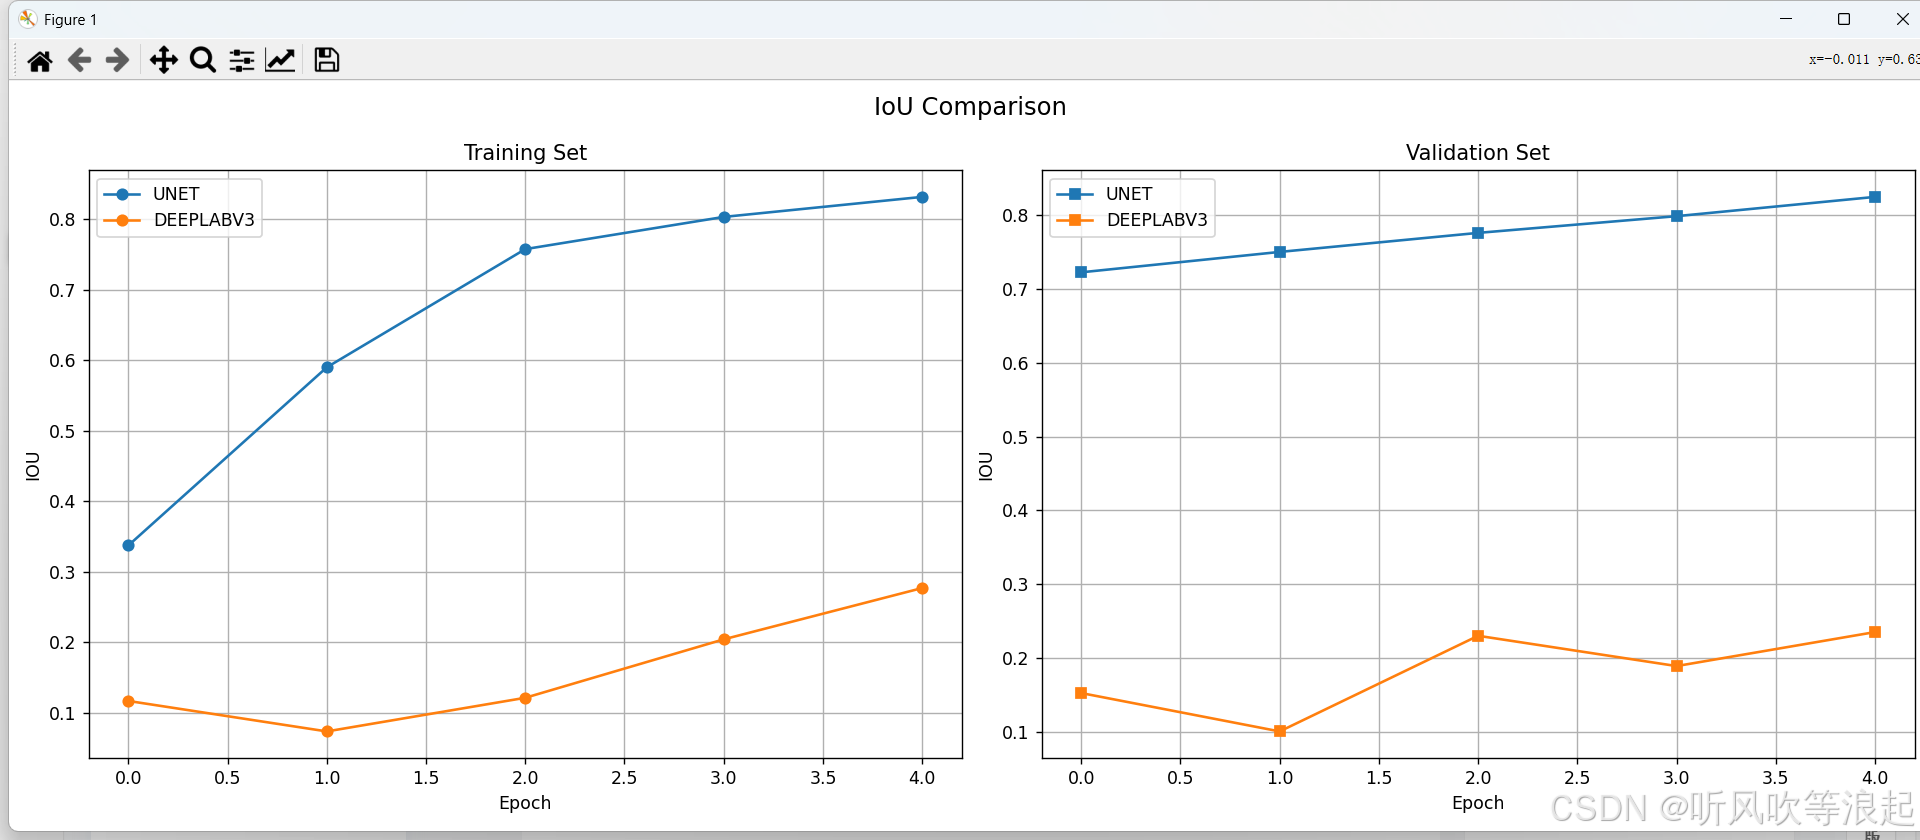

通过可视化工具可以直观比较不同模型的性能表现:

ax2.plot(epochs, values, label=model_name.upper())可视化结果通常显示:

- UNet在小数据集上通常收敛更快

- DeepLabV3在大数据集上表现更优

- 两种模型在不同指标上的曲线

这里仅仅训练了5个epoch用于测试代码的可行性,指标不做参考

3.对比